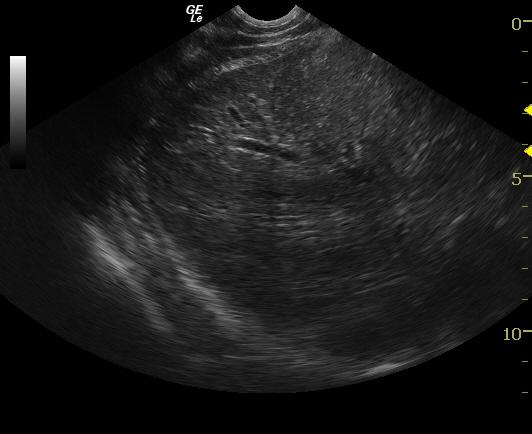

A 3-year-old FS Labrador Retriever dog with history of recent OHE, presented for seizure. Physical exam found patient emaciated, jaundiced, and with decreased skin turgor. In-house chemistry revealed markedly elevated Alkaline Phosphatase, ALT was unable to be determined, hypoamylasemia, low BUN, hyperbilirubinemia, and sample was icteric. CBC found high HCT, high RBC, and low MCHC. ALT analysis was sent out and showed marked elevation. Leptospirosis titer results were negative. Preprandial and postprandial bile acid profile results were both significantly elevated. Patient was admitted for I.V. fluid therapy and supportive care. Abdominal radiograph showed decreased detail and small spleen. Coagulation panel run awaiting ultrasound, found prolonged clotting time for PT. Patient continued on fluids, antidiarrheal medication, Lactulose, Vitamin K injections, and antibiotics. Physical exam the following day found patient BAR and extremely icteric.